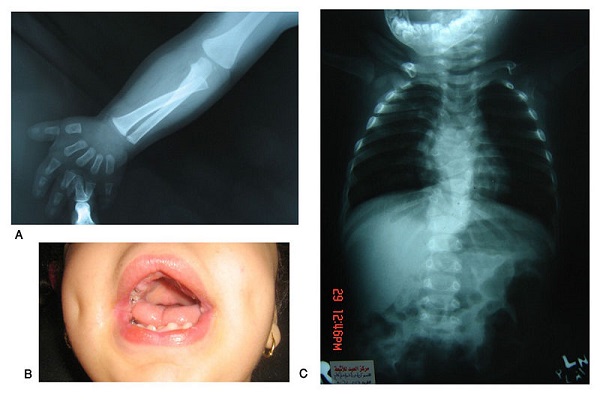

12- Síndrome de Pallister Killian

El síndrome de Pallister Killian tiene lugar debido a la anómala presencia de un cromosoma 12 extra en algunas células del organismo, dando lugar a diversas anomalías muscoloesqueléticas en cuello, extremidades, columna vertebral, etc.